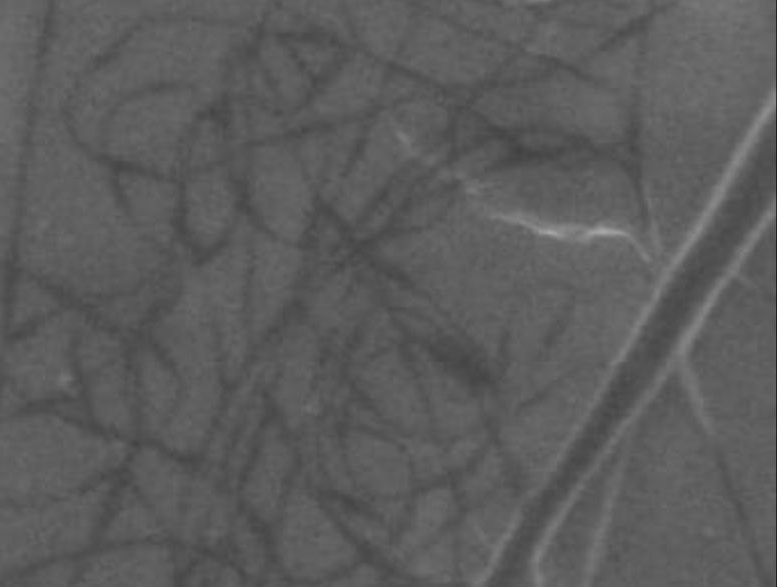

Morphology, size and size distribution of the nanofibres

Morphology analysis was adapted from Aytac et al. (2019) [38]. The SEM analysis was conducted to detect electrospun nanofibers' fibre shape and diameter. The electrospun nanofibres from 18 runs were investigated individually by SEM (FEI, quanta 450, Czech). Images revealed the morphology of resultant nanofibers and measured their diameters in nanometres. The average number of records was calculated using a standard deviation estimation. The setting of the SEM machine was conducted on voltage 25.00 kv, magnification 23624 and width (8.3-9.3 mm).

Results of the SEM analysis are listed in table 2, with a wide range of fibre diameters starting from 87.2 nm (run 13) to 2500 nm (run 18). Run 18 did not produce true nanofibers due to the deficient concentration of PVA. The statistical analysis revealed that the effect of each polymer (factor) on the diameter size of the electrospun nanofiber was vast. Therefore, there is a correlation between factors A, B and C and fibre diameter as expressed in equation 5.

Fig. 3: Nanofibres SEM images with nanofiber diameter frequencies. The PVA, PEO and HPMC were symbolised as V, E and P. Data are given in mean±SD, n=3

The morphology of nanofibers would be affected by device parameters such as flow rate, voltage and distance from the collector. Also, nanofibres' properties could be changed due to temperature and humidity. The bead formation appears with a low concentration of PVA (run 2) or a high concentration of PEO and HPMC (runs 6 and 11), as shown in fig. 3. Therefore, increasing PVA concentration leads to beads' disappearance and smooth fibres' formation. Nageeb El-Helaly (2021) and Silva J. A. et al. (2021) reported similar results [47, 48]. Kalluriet al.(2021)[49] studied the relationship between the fibre diameter, bead diameter and flow rate. Thus, they concluded that better fibre uniformity and bead formation were needed at a high flow rate. These results appear clearly in run two and run six and agree with Silva et al.(2021) results [50], who reported that only the concentration of PVA (≥ 15%) could produce uniform nanofibers when using the lower molecular weight of PVA (67,000). Fibre diameter of 15% PVA and more appeared to be in the range 87.11 to 252.5 nm with uniform fibres and disappearance of beads except in run 6, where the beads appear due to increasing the concentration of HPMC as highlighted by Gripet al. (2018) [46].